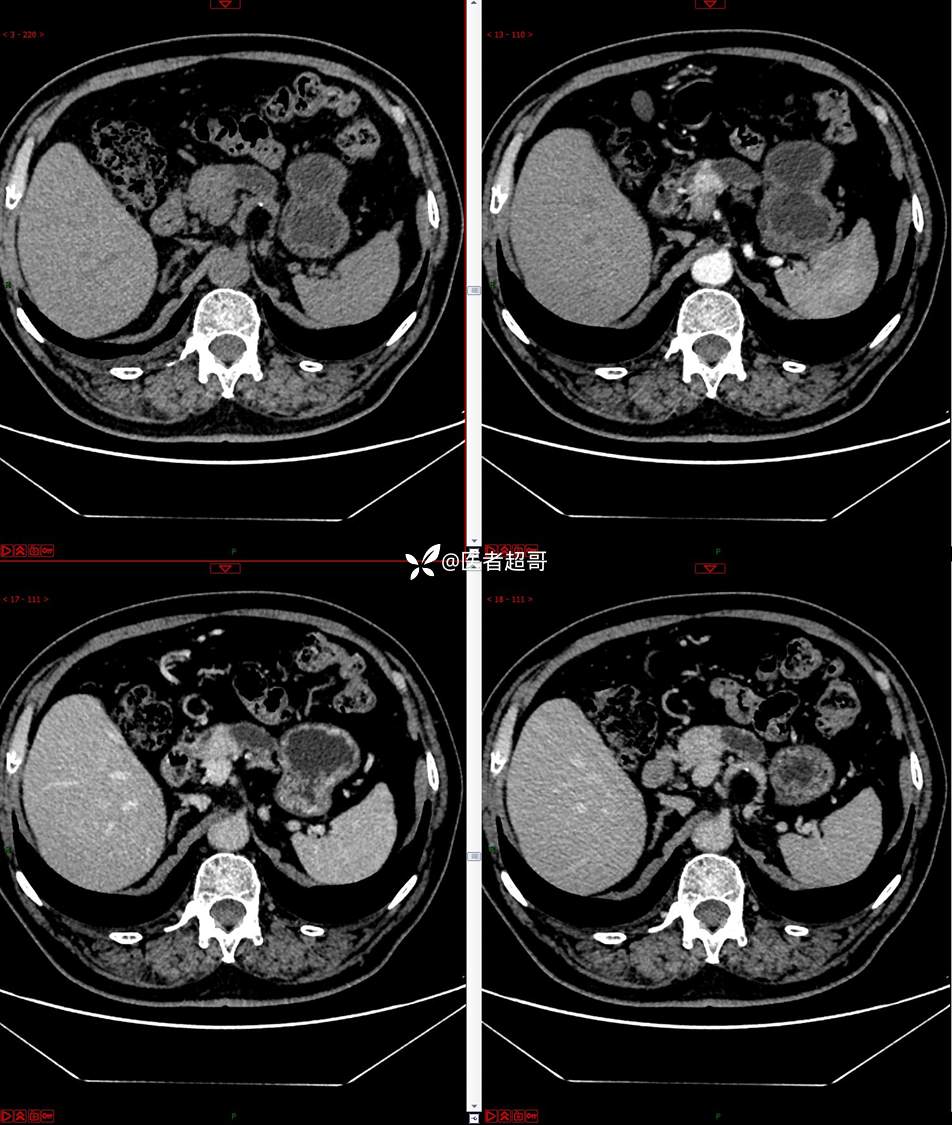

【影诊笔记677】查体发现胰腺占位性病变1周,细节决定成败,请诊断分析!

主 诉:查体发现胰腺占位性病变1周。

现病史:患者1周前在当地查体时发现胰腺占位性病变,无恶心、呕吐,无腹痛,无寒战、高热,无咳嗽、咳痰等异常不适,来我院门诊查上腹部CT平扫+强化:胰腺尾部异常密度灶。今为求进一步治疗,门诊以“胰腺占位性病变”收入院。患者自发病以来,一般情况可,神志清,精神可,普通饮食,二便正常,体重及体力无明显改变。

既往史:既往糖尿病病史2年,口服二甲双胍早晚各一片和格列吡嗪早晚各一片,否认高血压、心脑血管病等疾病史,否认肝炎、结核或其他传染病史及密切接触史,预防接种史不详,否认药物及食物过敏史,否认外伤史,12年前肾癌切除术手术史,否认输血史,其它无特殊。